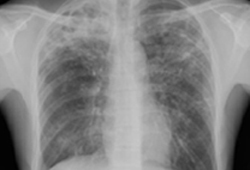

[Figure caption and citation for the preceding image starts]: Opacities in right lower lobe in a patient with pulmonary TB and diabetesFrom the personal collection of David Horne and Masahiro Narita; used with permission [Citation ends].